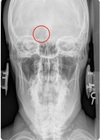

2

3

4

5

Perfectly

Q

Lateral cervical view

A

angle of mandible

How well did you know this?

1

Not at all